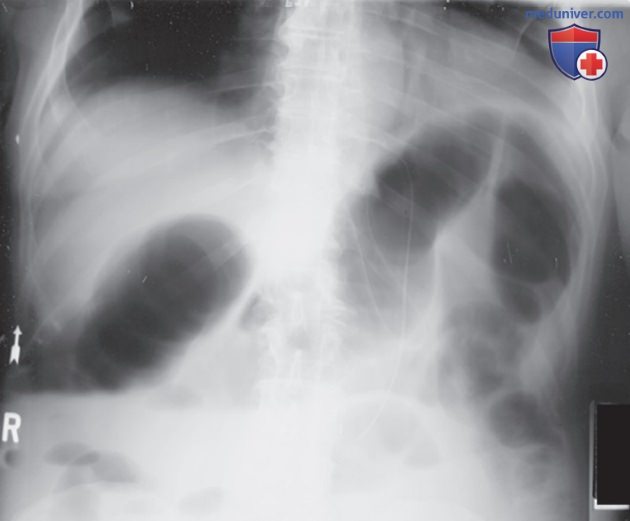

Рисунок 7. Рентгенограмма правого коленного сустава в косой передне-задней проекции, демонстрирующая произвольное движение пациента.

Пространственное разрешение рентгенограммы при оценке ее качества